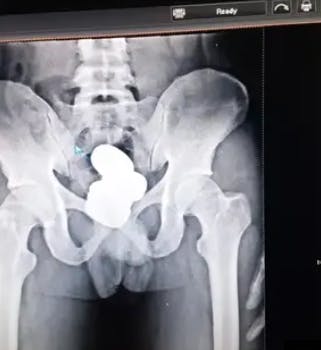

Et røntgenfoto afslørede, at manden skjulte nogle metalliske genstande i sin krop.

Artiklen fortsætter under billedet

Røntgenbilleder afslørede, at manden smuglede noget i endetarmen. Foto: CISF